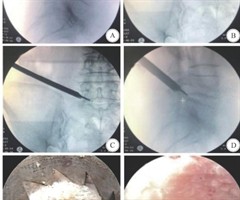

脊柱内镜TESSYS-ISEE与传统TESSYS技术治疗腰椎间盘突出症疗效的对比研究

【摘要】目的对比脊柱内镜经椎间孔内镜脊柱系统-集成脊柱内镜进化(TESSYS-ISEE)技术与传统TESSYS 技术治疗腰椎间盘突出症(LDH)的安全性及临床疗效。方法回顾性分析 2019年1月—2025年1月于南京脑科医院神经外科进行的符...